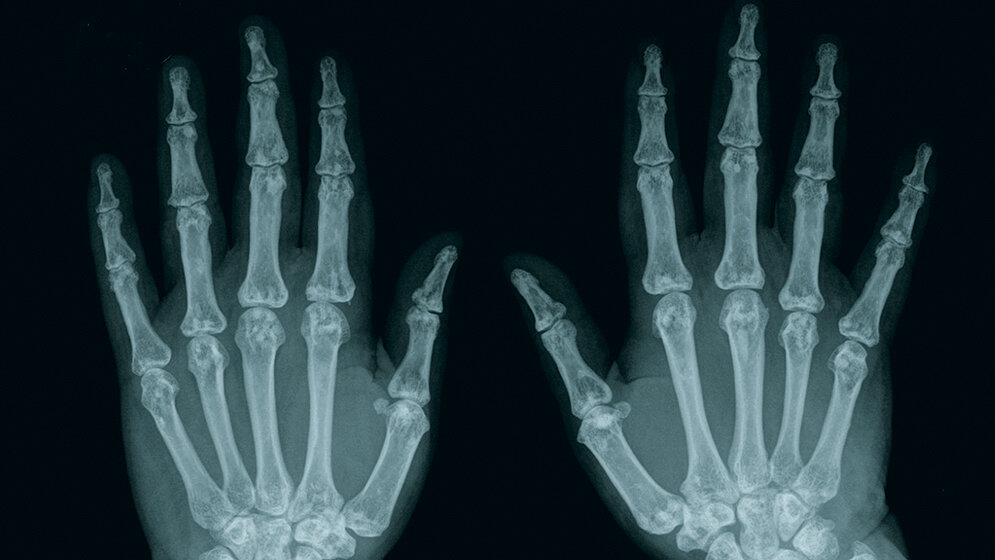

Die Osteopoikilie ist eine seltene, autosomal dominant vererbte Störung des Knochengewebes unbekannter Ätiologie, die bei radiologischen Untersuchungen als Zufallsbefund gesehen wird. Die Läsionen sind hauptsächlich im Bereich der Epi- und Metaphysen auffällig. Sie sind multiple, meist kleinere, gut abgrenzbare, variabel geformte und ausgebreitete Sklerosen des Skeletts.

Osteopoikilosis is a very rare autosomal dominant disorder of unknown etiology wich is found on radiological examination. The lesions were more obvious at the epiphysis and metaphysis. They presenting as multiple, small, well-defined, variable shaped and widely distributed sclerotic areas throughout the skeleton.